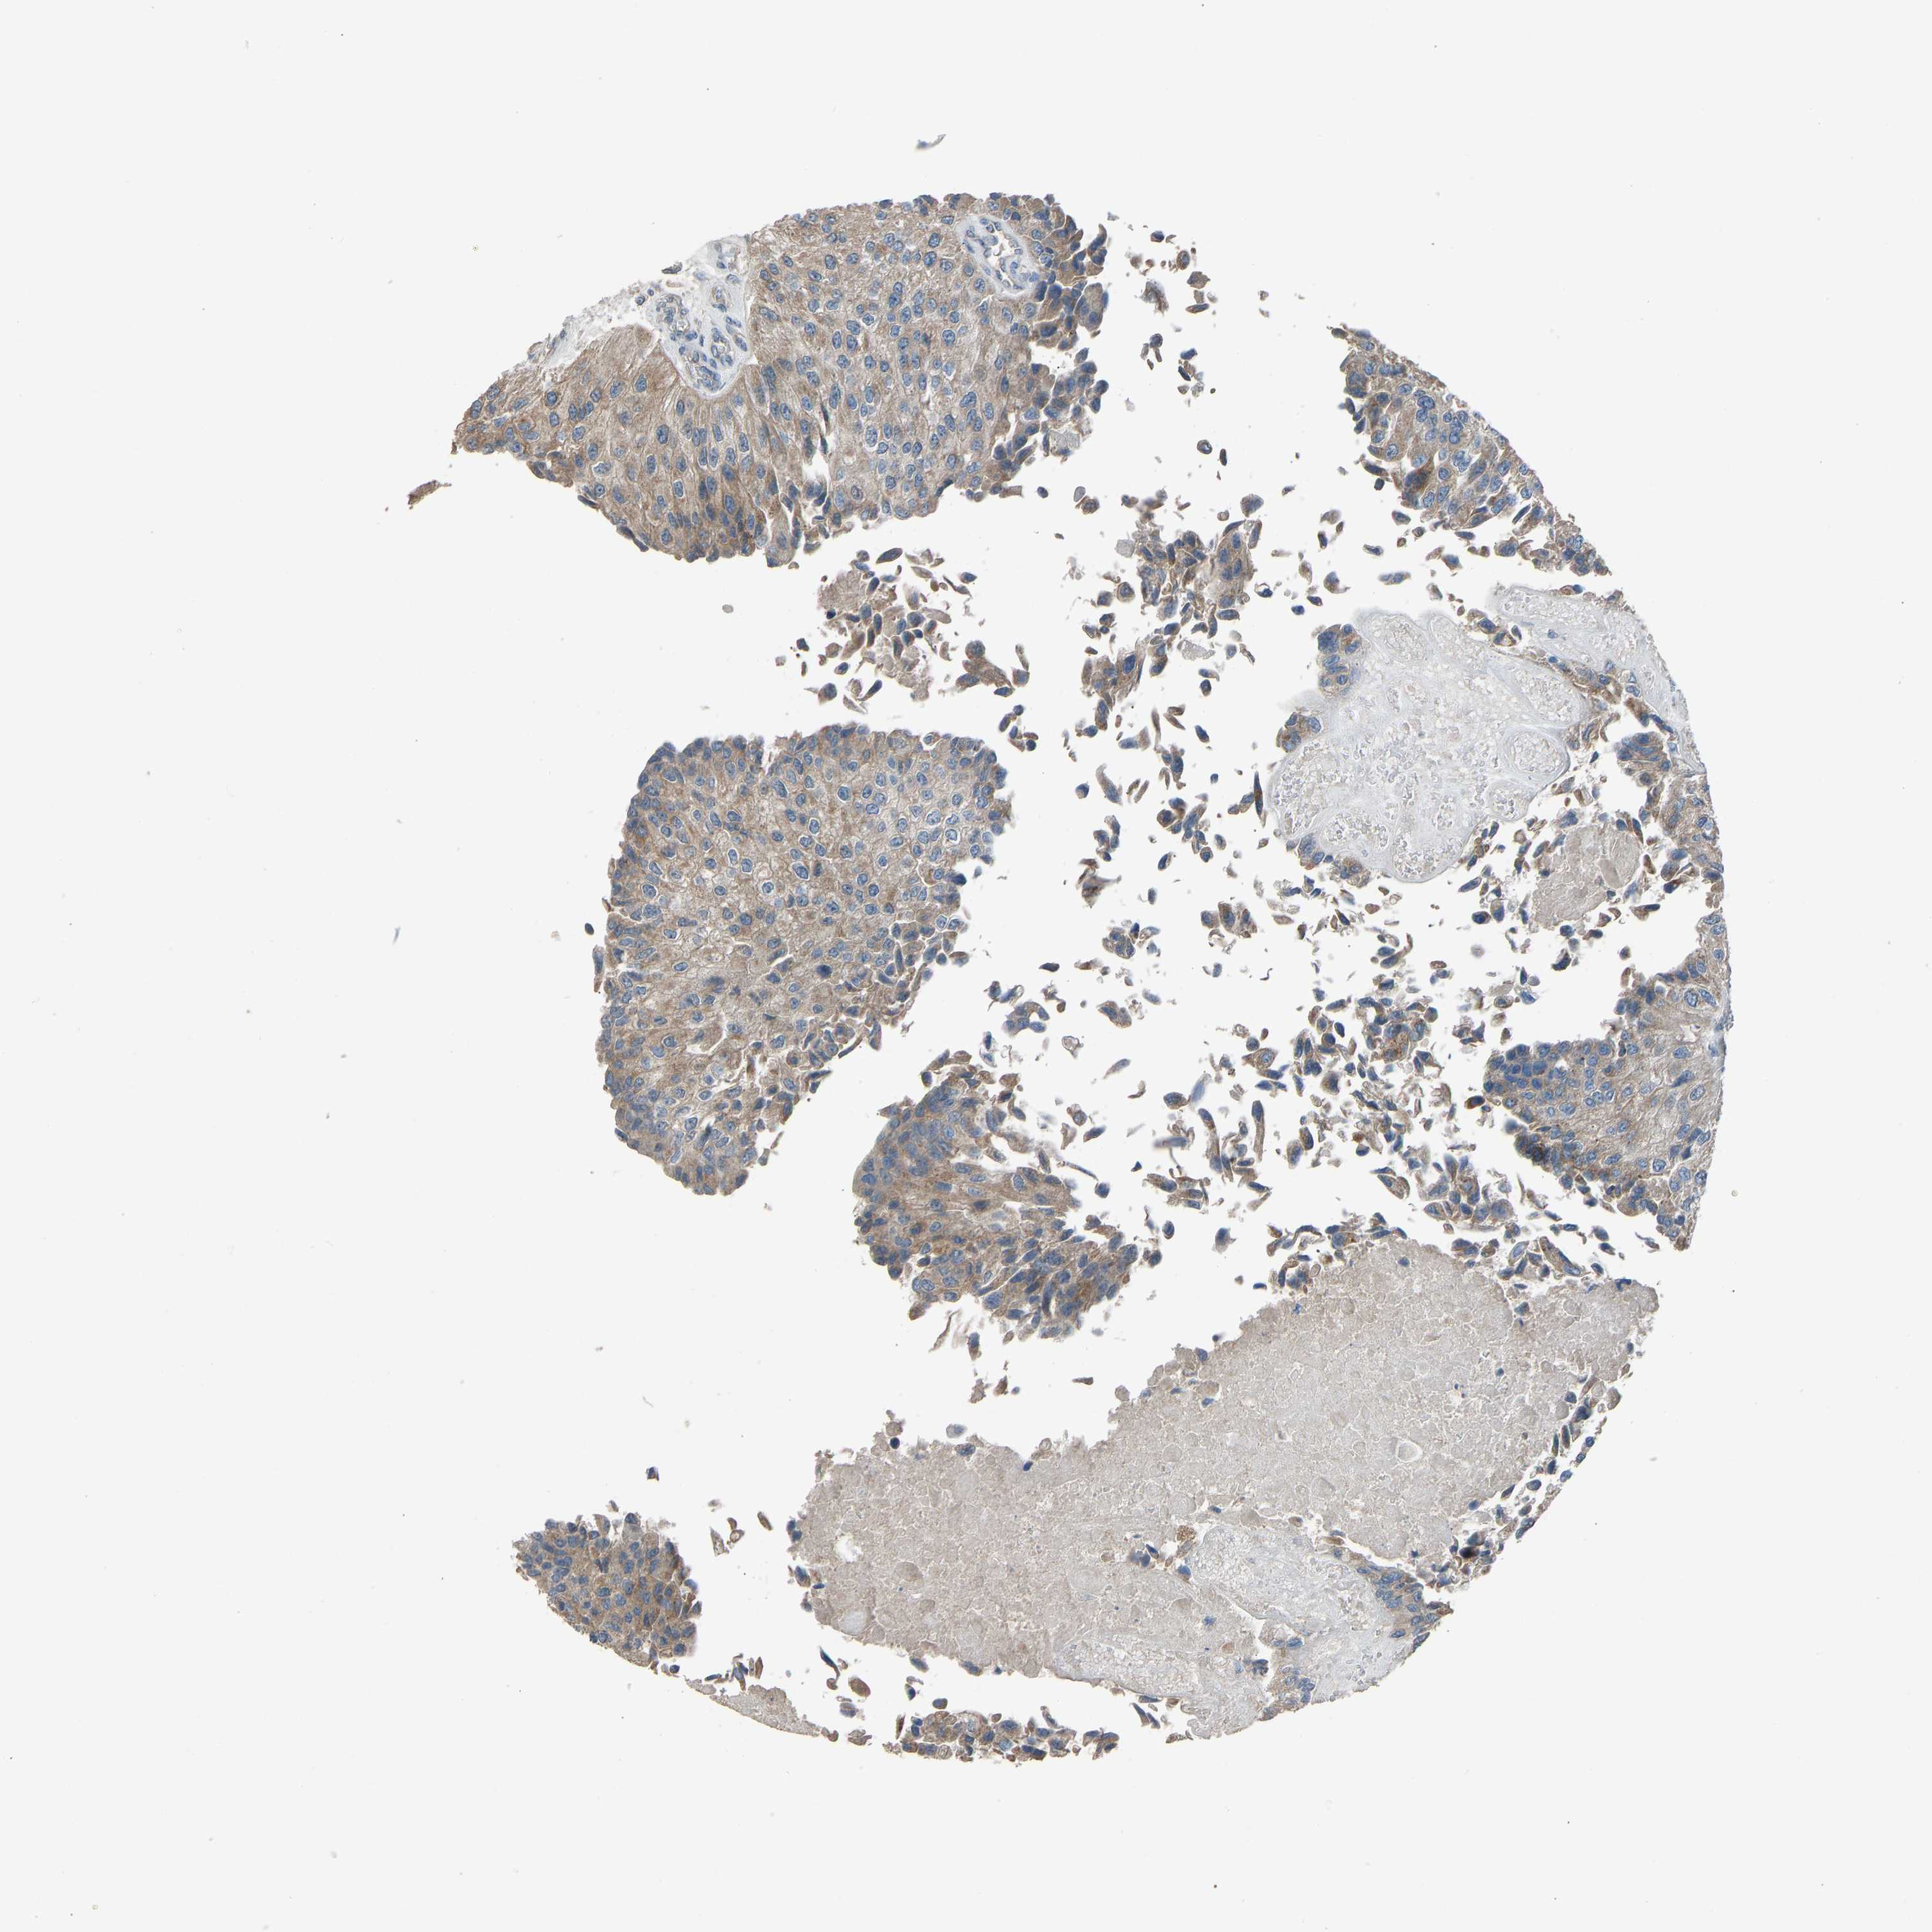

UROTHELIAL CANCER - Protein expressioni

A mouse-over function shows sample information and annotation data. Click on an image to view it in a full screen mode. Samples can be filtered based on level of antibody staining by selecting one or several of the following categories: high, medium, low and not detected. The assay and annotation is described here.

Antibody stainingi

Antibody staining in the annotated cell types in the current human tissue is reported as not detected, low, medium, or high, based on conventional immunohistochemistry profiling in selected tissues. This score is based on the combination of the staining intensity and fraction of stained cells.

Each image is clickable and will lead to virtual microscopy that enables deeper exploration of all samples and also displays staining intensity scores, fraction scores and subcellular localization as well as patient and tissue information for each sample.

Antibody HPA008257

Antibody CAB018971

Urothelial carcinoma, Low grade

Urothelial carcinoma, High grade